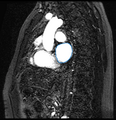

The objective of this project is to automatically segment the scar created by RF ablation in delayed enhancement MR images acquired after the procedure. We would then be able to present the surgeon with a visualization showing the size, shape and location of the scar.

Given corresponding cardiac blood pool and post-procedure delayed enhancement images for each patient, our plan is to first segment the LA in the blood pool image, then transfer this segmentation to the delayed enhancement image of the same patient. We intend to use this prior information while searching for the ablation scar using intensity based algorithms. This prior knowledge of the LA location will allow us to avoid most false positives.

• Performed ablation scar segmentation experiments by using the LA segmentation as a spatial prior to limit the search space. Although we attempted several methods, the best results were obtained by finding a threshold that most separated the intensity histograms of normal LA and scar tissue in the delayed enhancement image. This gives results that are fairly close to expert segmentations.